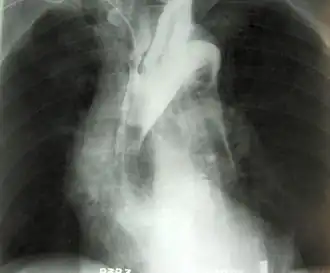

Een aneurysma (Grieks ἀνεύρυσμα, meervoud aneurysmata) is een plaatselijke verwijding van een (meestal) slagaderlijk bloedvat, als gevolg van een ter plaatse zwakke vaatwand. Het meest voorkomend is een aneurysma van de aorta, de slagader in de buik of het abdomen. Men spreekt in dat geval van een abdominaal aorta-aneurysma (AAA). Een aneurysma van de aorta ter hoogte van de borstkas, is een thoracaal aorta-aneurysma (TAA). Een aneurysma gaat meestal niet gepaard met klachten.

Een aneurysma van de lichaamsslagader in de buik, ofwel een aneurysma aortae abdominalis, heeft men meestal zonder symptomen. Mensen met een AAA weten dan ook meestal niet dat zij een aneurysma hebben. Soms worden klachten als een kloppend gevoel in de (boven)buik of pijn in de rug, door het drukken van het aneurysma op de wervelkolom, beschreven. Meestal is een gevonden AAA een toevalsbevinding bij radiologisch onderzoek voor een andere medische indicatie, zoals een echografie van het hart (een echocardiografie) of een CT-scan van de nieren. Als de grootte van het aneurysma toeneemt, verzwakt de vaatwand ter plaatse verder, en kan er een scheur in de vaatwand ontstaan. Dit is een levensbedreigende situatie, waarbij er door bloeding een tekort aan circulerend bloed ontstaat, met weefsel-/orgaan-schade en zelfs de dood tot gevolg. Een scheuring van het aneurysma is lastig te herkennen, maar alarmsignalen zijn flauwvallen/bleekheid, en acute pijn in de buik of in de onderrug. Bij een aneurysmaruptuur van de aorta in de buik is deze bloeding in 75% van de gevallen dodelijk. Meer dan 50% van de patiënten overlijdt voor aankomst in het ziekenhuis, waarna nog eens meer dan 50% van de geopereerden overlijdt tijdens de operatie. Een aneurysmaruptuur in de ribbenkast (borstholte) is vrijwel altijd dodelijk.

Diagnose (opsporing) en behandeling van een AAA

Vanwege het levensbedreigende karakter, is het aan te raden een verdenking op een aneurysma goed te laten onderzoeken. Lichamelijk onderzoek alleen sluit een aneurysma nooit uit. Als gouden standaard voor het aantonen van een aneurysma wordt een echografie van de buik gebruikt. Hierbij kan men nauwkeurig de juiste diameter van het verwijde bloedvat bepalen. Hierbij houdt men de grootst te meten voor-achterwaartse diameter, de Anterior-Posterior- of AP-diameter, aan. Als arbitraire grens wordt een diameter van 55 mm gebruikt bij mannen en 50 mm bij vrouwen. Uit onderzoek is gebleken dat vanaf deze diameter het risico op een vaatbreuk of ruptuur reëel is, en de risico's van een operatie niet meer opwegen tegen het risico op scheuren.

Een CT-scan met contrastvloeistof laat precies zien hoe de vaatboom rond de aorta eruitziet. Dit bepaalt ook of men laparo-tomisch, via het openen van de buikholte, of endovasculair (vanuit de vaten na benadering in de liesslagader(s)) opereert. Men kiest respectievelijk voor het inhechten van een aortabifurcatieprothese, ook wel broekprothese genoemd, of een endovasculaire stent op maat. Laatstgenoemde procedure staat bekend als EVAR; Endovascular Aneurysm Repair.